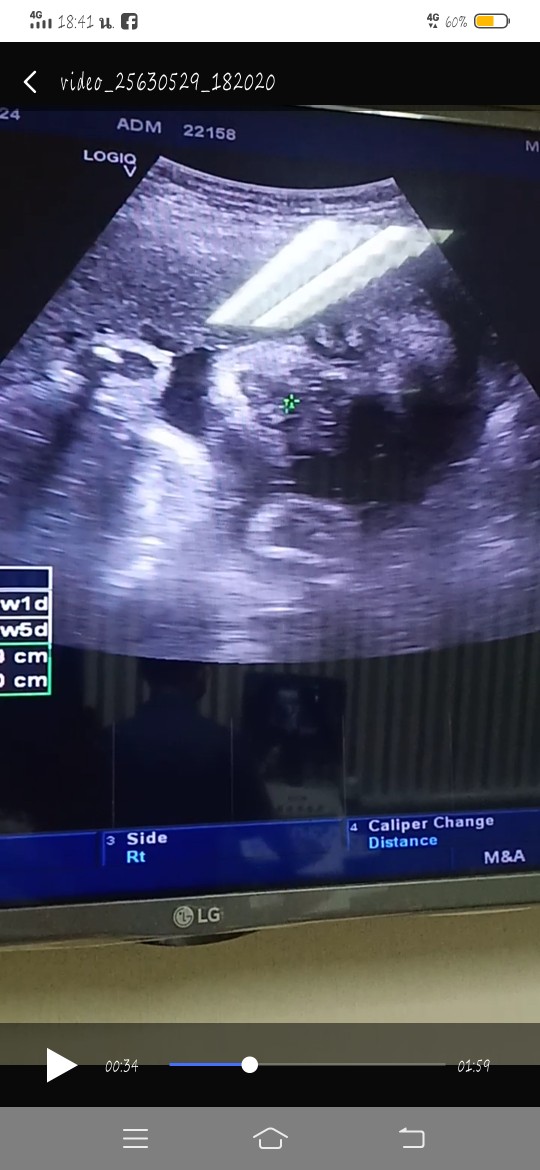

33+2วีค 13สิงหาค่ะ